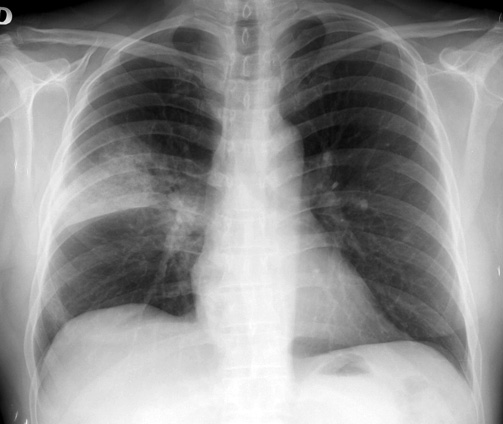

Los resultados de este ensayo clínico aleatorizado indican que la vacuna PPV23 no redujo las tasas de síndrome coronario agudo (fatal y no fatal) ni de ictus isquémico, si bien el estudio presentaba una baja potencia estadística. JAMA Cardiology, 17 de septiembre de 2025.

EClinicalMedicine, 1 de enero de 2019 La vacuna neumocócica polisacárida 23-valente ofrece protección moderada a corto plazo contra la enfermedad neumocócica invasiva (ENI) en adultos mayores. Los serotipos PPV23 comprenden una proporción cada vez mayor de casos de ENI en adultos mayores debido a la sustitución de serotipos después del uso rutinario de vacunas conjugadas neumocócicas en niños.

La vacuna redujo en un 33% las neumonías por serotipos incluidos en la vacuna, y en un 27% el total de neumonías por neumococo en esta población. Lancet Infectious Diseases, 23 de enero de 2017